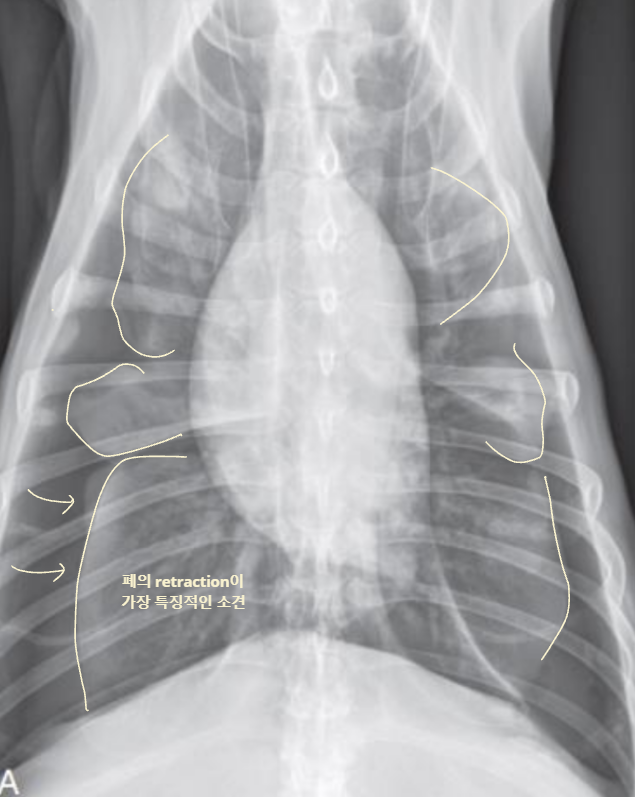

Radiographic signs

interlobar fissure 두껍게 관찰되고,

흉벽이 떨어져 나간 것처럼 보임

심장이 떠 있고, 폐가 쪼그라듦

- Interlobar fissure widening

- Lung retraction

- Pleural wall thickening

- Scallop sign

- Cardiac effacement

- Blunt angle

- Retraction of pleural surface

- Collapsed lung (→ opacity 증가)